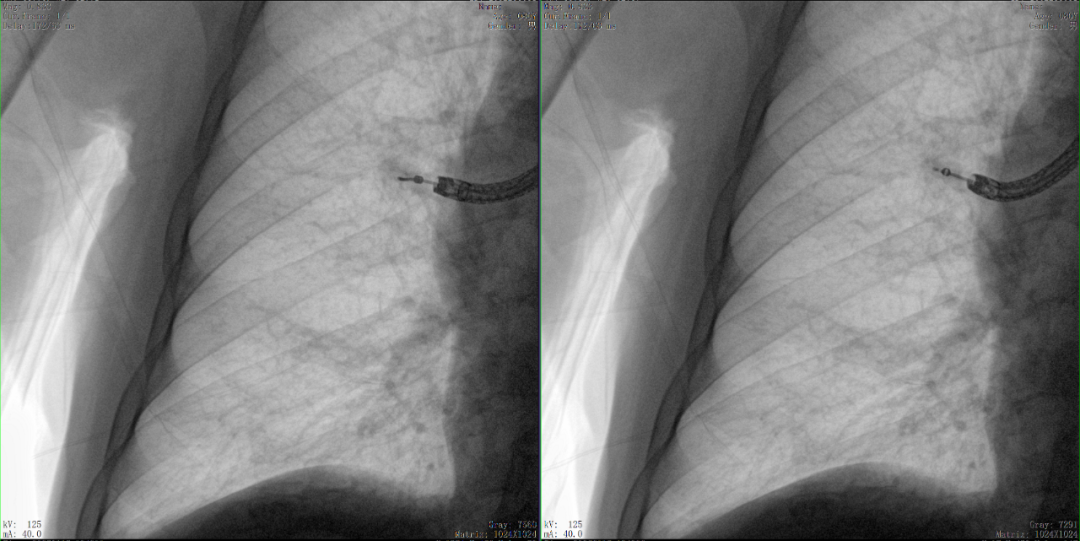

病例3:超聲支氣管鏡下肺活檢(80歲)

三維C形臂還可以創新性地應用在呼吸介入領域。例如,在經皮穿刺或經支氣管鏡肺結節活檢、定位、消融等場景中,用于確認工具是否到達病灶、消融范圍是否完全覆蓋病灶等。

二維C形臂圖像

二維影像無法準確判斷工具是否到達病灶

三維C形臂圖像

三維各切面影像都顯示工具達到病灶內